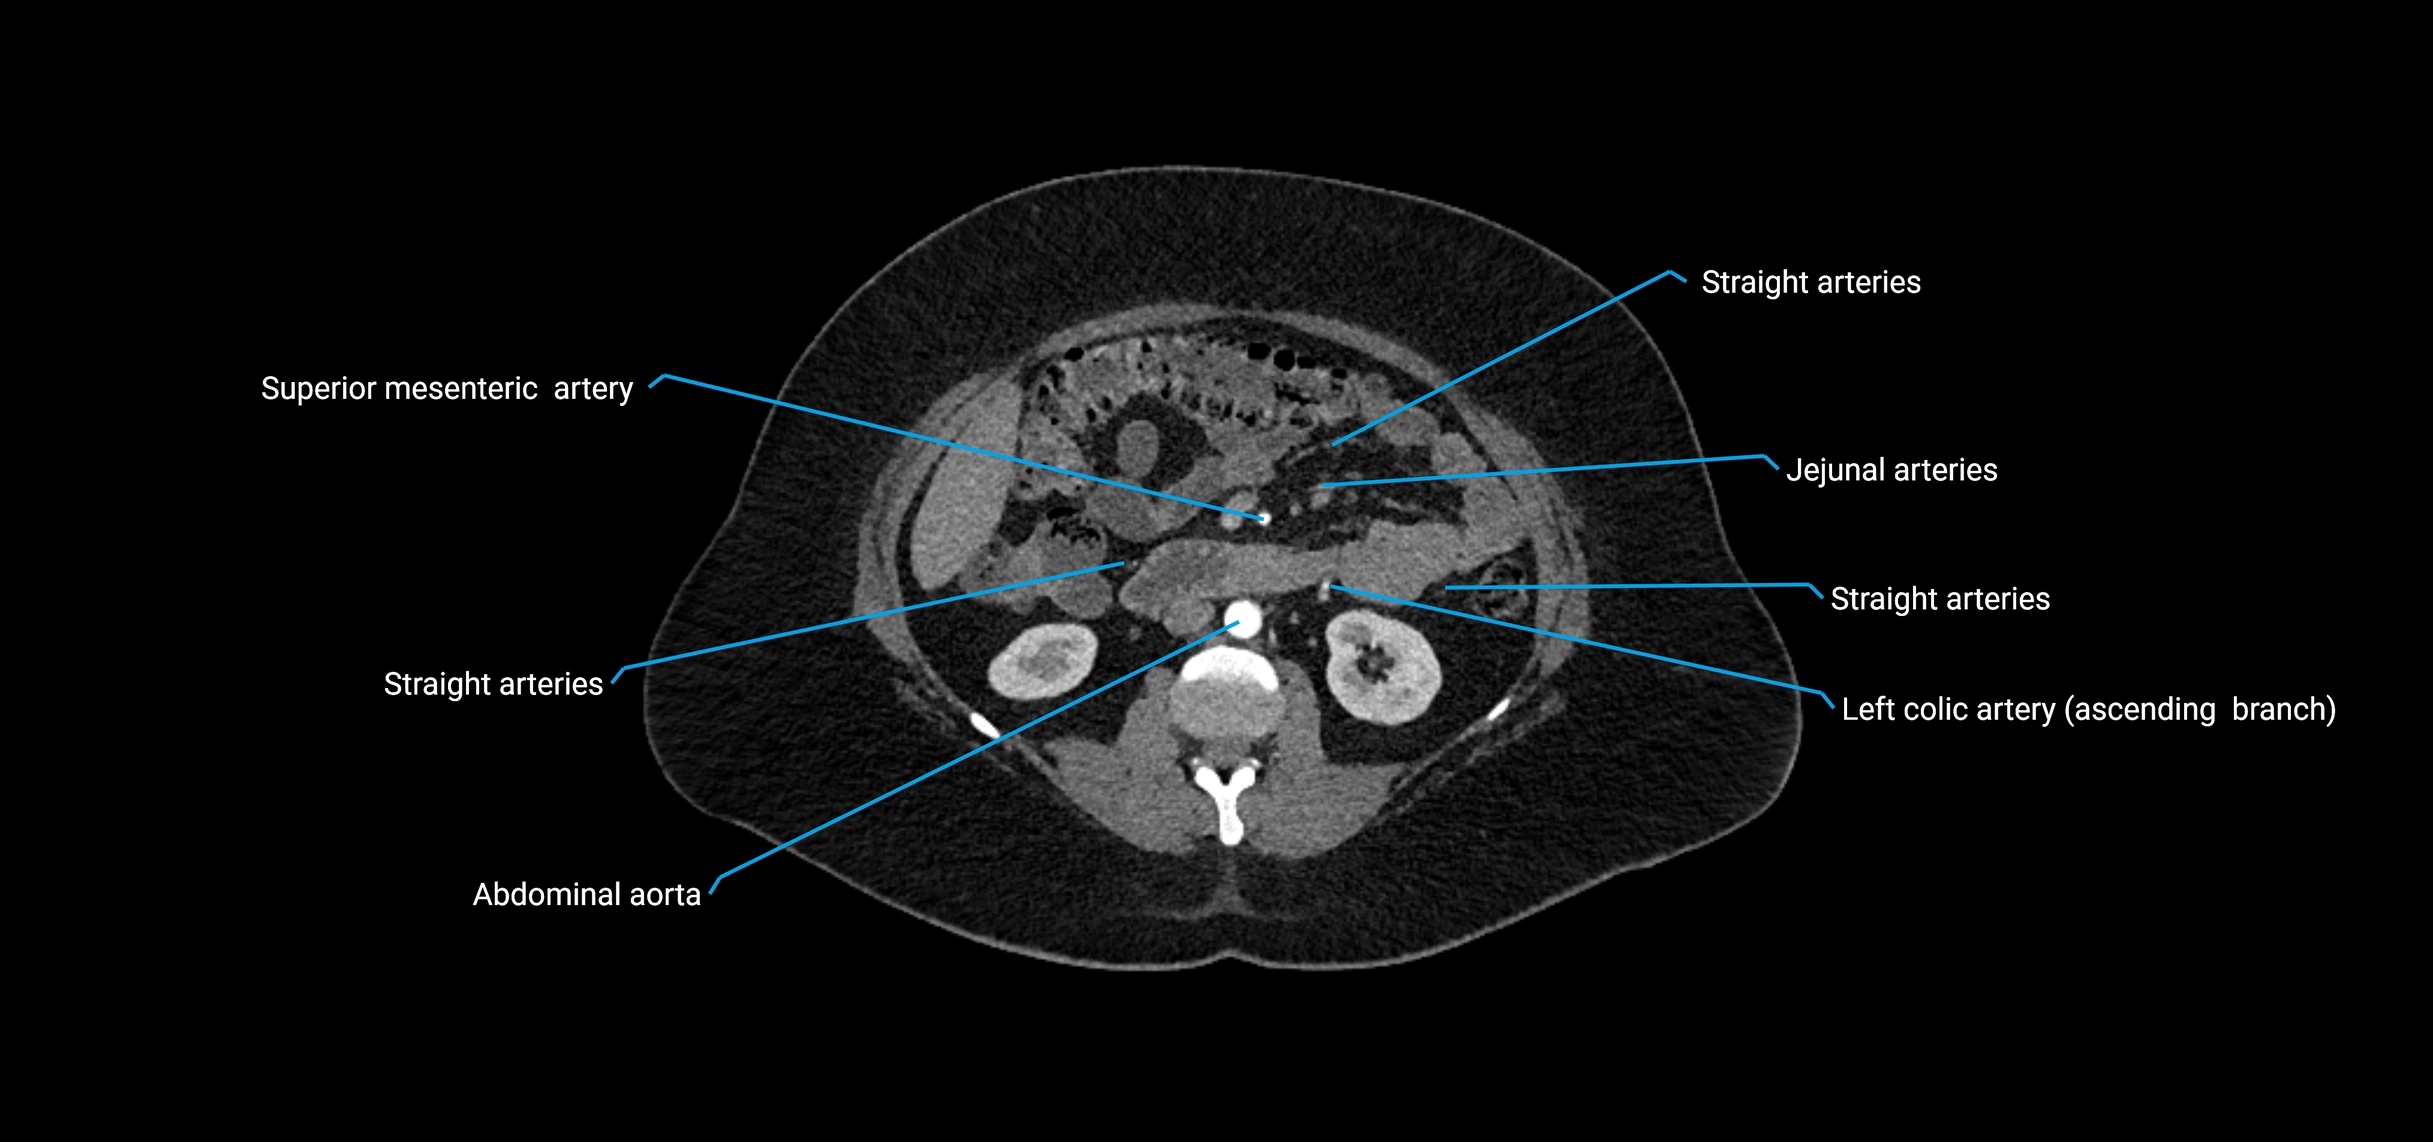

Contrast-enhanced CT (CTA):

• Gold standard for abdominal aortic imaging

• Provides excellent detail of lumen, wall, aneurysm, thrombus, and branch vessels

• Multiplanar and 3D reconstructions help in aneurysm measurement, stent graft planning, and dissection evaluation